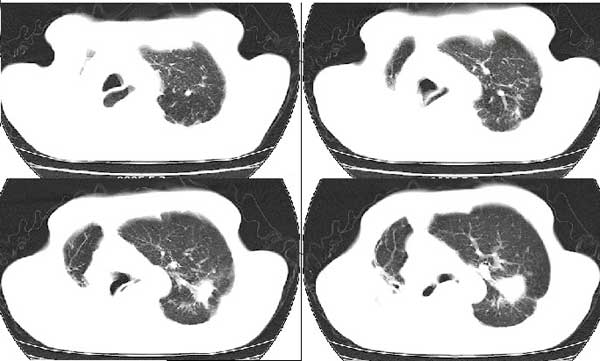

以下是引用扬仪在2005-5-12 20:46:40的发言:[br]右肺呈术后改变;双侧肺野散在分布斑片状、点状高密度病灶,(似可见“树芽征”);左上尖后段见斑团状高密度病灶(2个层面?),边缘毛糙,段性分布,与斜裂相邻,临近胸膜粘连;增强示病灶边缘强化,内呈水样密度;心影、纵隔右移,内可见4r淋巴结肿大。[br]意见:1、双肺继发性肺结核,左上为干酪病灶;[br] 2、矽肺合并感染;[br] 3、建议抗痨+抗炎。 [br]愚人之见,请高人指教!